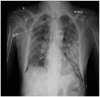

Coronavirus disease-19 caused by severe acute respiratory syndrome Corona virus-2 is characterised by wide heterogeneity in clinical presentation. The typical radiographic findings in COVID-19 include bilateral ground-glass opacities and/or consolidations predominantly affecting the lower lobes and posterior segments of lungs. Other rare abnormal radiographic findings include pneumothorax, pneumomediastinum and pneumopericardium. There has been an increased incidence of pneumomediastinum, a rare but potentially life-threatening complication during this pandemic. It may be spontaneous or secondary. Pneumomediastinum may be due to barotrauma, cytokine storm induced diffuse alveolar injury or direct viral infection of type I and type II pneumocytes. The presence of pneumomediastinum in COVID-19 patients may indicate extensive alveolar membrane destruction and those patients need close monitoring. There are no consensus guidelines in managing COVID-19 patients with pneumomediastinum. Higher mortality rates (70.58%) are reported in intubated COVID-19 patients with pneumomediastinum. The development of pneumomediastinum in COVID-19 should be considered as a poor prognostic factor.